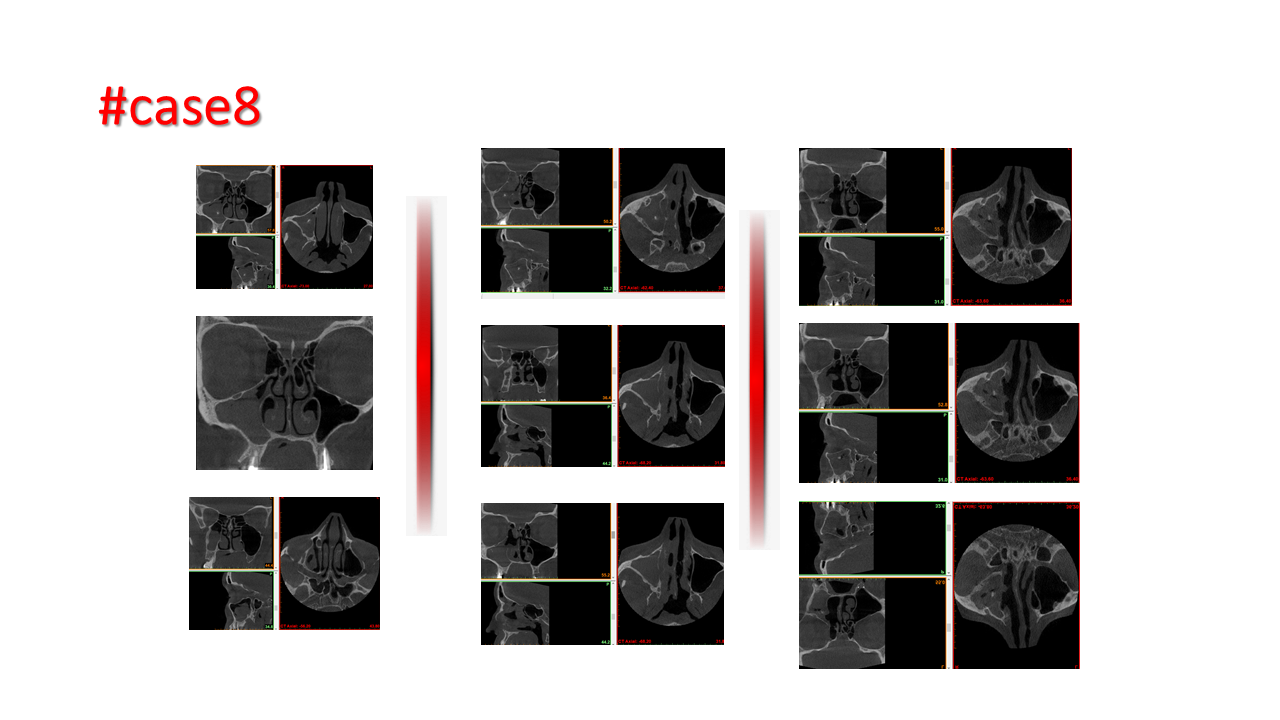

FESS Case Review and Radiologic Analysis (30.09.2016)

Case-based presentation focused on pre- and postoperative imaging in functional endoscopic sinus surgery (FESS). Includes anatomical landmarks, surgical variations, sinus pathology, and technique evaluation. Delivered by Dr. Levon Galstyan at AAOMFS.